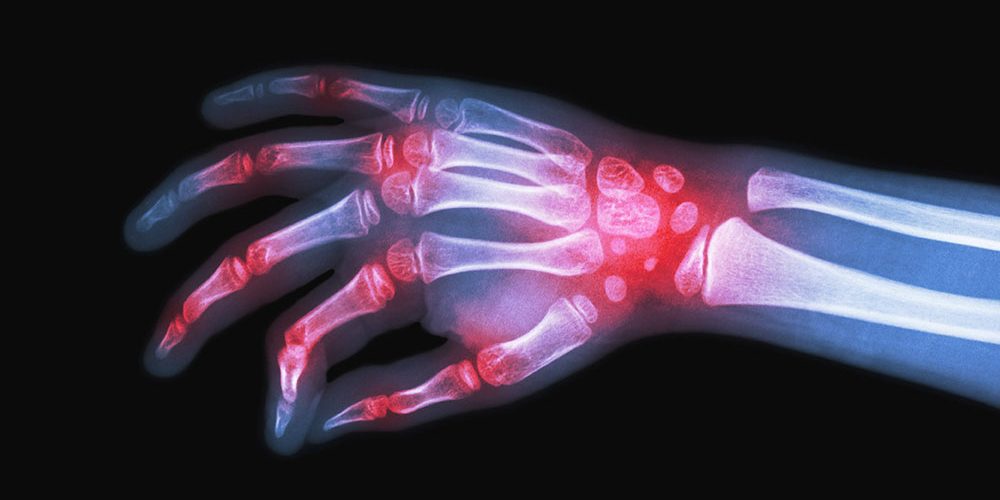

Dia Mundial da Artrite Reumatoide: Sociedade Brasileira de Reumatologia (SBR) alerta: diagnóstico precoce e tratamento adequado podem permitir qualidade e vida produtiva

O alerta vale para todas as doenças reumáticas e a SBR recomenda que, na presença dos sintomas, o paciente procure um reumatologista Neste sábado, 12 de outubro, é celebrado o Dia Mundial da Artrite Reumatoide, criado para chamar a atenção da população sobre esta doença de natureza inflamatória, crônica e progressiva, que acomete cerca de…